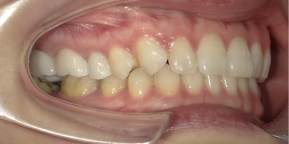

29歳女性のビフォーアフター

| 診断 | 叢生(デコボコがある状態)、過蓋咬合 |

| 治療方針 | インビザラインシステムにて主にIPR(歯と歯の間をわずかに削合してスペースを獲得する方法)を組み込んだ動的矯正治療を行い、叢生を改善後、保定を行う。臼歯部の咬合関係はプランの関係上維持して叢生と前歯部の咬合改善を目指した。 |

| 治療費 ※ | 60万4千円(診断、型取り、PMTC、保定装置を含む料金) |

| 治療期間 | 1年5か月 |

| リスク | 1日20時間以上マウスピースを使用できない場合、歯が動かない可能性がある。装着時や食事時に痛みを伴う。歯肉退縮や虫歯になるおそれがある。また、指導通りに装着できていない場合や適切なブラッシングが出来ていないとそのリスクが高くなる。歯根が短くなることがある。ごくまれに歯の神経が損傷してしまうことがある。過去にぶつけたり深い虫歯治療をしたことがあるとそのリスクはやや高くなる。矯正後には保定装置が必要。適切な使用ができない場合、後戻りの原因となる。将来的に歯並びが動いて再矯正が必要な場合がある。親知らずが正常に生えていない場合、その可能性がやや高くなる。 |